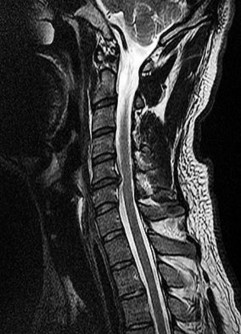

A 65-year-old male presents with progressive clumsiness in his hands, difficulty buttoning his shirt, and a wide-based gait. Physical exam reveals a positive Hoffmann's sign bilaterally.

MRI of the cervical spine demonstrates multilevel degenerative spondylosis with cord compression. Which of the following MRI findings is considered the strongest independent predictor of a poor neurologic recovery following surgical decompression?